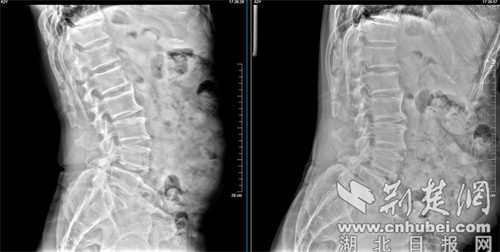

经人介绍,张先生来到襄阳市中医医院脊柱骨科就诊。经过详细的体格检查及影像学评估,张先生被确诊为腰椎滑脱症合腰椎椎管狭窄症。病变节段主要位于L4/5(腰4/5节段)。 影像显示,该节段的椎间盘退变严重,椎间隙高度塌陷,并伴有黄韧带肥厚,导致椎管内的神经根受到严重压迫。这正是导致张先生长期疼痛和无法行走的根源。

检测报告。通讯员 供图